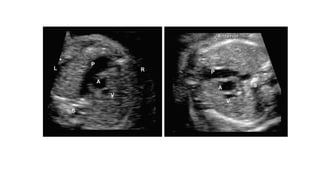

• #14 Figs A to C: Determination of the fetal right and left side by use of method described by Cordes et al. (A) The fetal head is aligned to the right of the screen The transducer is then rotated clockwise by 90° to obtain an image in the transverse plane at the level of the abdomen; (B) The spine is identified (yellow arrow), going clockwise from the spine is the right side followed by the left; (C) Showing diagrammatic representation that demonstrates the right and left sidedness according to the position of the spine in the transverse plane.

• #16 Heart Position and Axis. Normal position and axis of the heart. The heart is predominantly in the left side of the chest, with the apex of the heart pointing leftward. Dual-screen image shows the stomach also on the left side.